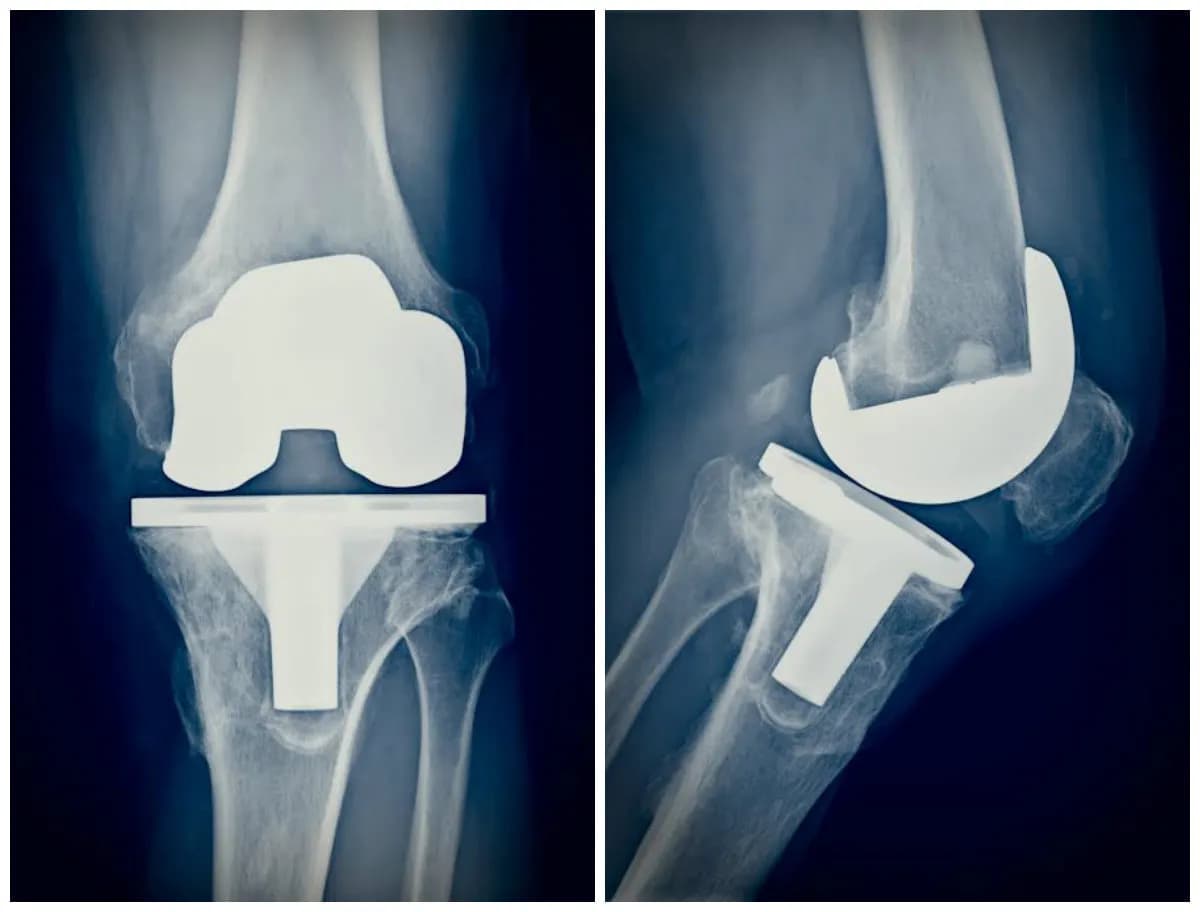

Tag badania przed operacją kolana